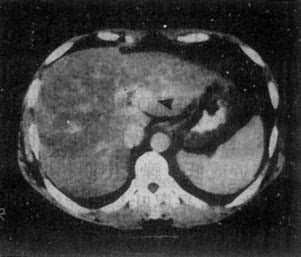

肝脏增强ct如何鉴别肝癌与肝血管瘤肝癌CT的影像学特征是平扫时呈低密度,增强扫描时造影剂呈 快进快出 表现。肝脏血管瘤的特征是平扫时呈低密度,增强扫描时造影剂呈“